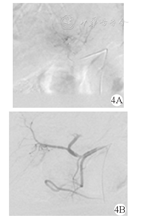

患者 男,57岁,乙型肝炎病史20余年。患者以"右上腹不适1周"为主诉入院。上腹部平扫CT(2015年10月21日)示:肝内Ⅳ段及Ⅷ段交界处可见8.2 cm × 6.2 cm团片状低密度区(图1A、图1B)。上腹部增强MRI(2015年10月22日)示肝左叶团块影,增强扫描病灶边缘不规则强化(图1C、图1D)。实验室检查:乙型肝炎表面抗原(HBsAg)阳性,甲胎蛋白(AFP)833.40 μg/L,癌抗原(CA)19-9 108.58 kU/L,肝功能Child-Pugh分级B级。临床诊断为原发性肝细胞癌,巴塞罗那肝癌分期(BCLC)B期。患者无介入治疗禁忌证,于2015年10月29日行肝动脉化疗栓塞术(TACE),术中造影见肝内肿瘤轻度染色(图2A),超选后肝右动脉予以碘化油5 ml +吡柔比星5 mg缓慢栓塞,辅助明胶海绵微粒(350~560 μm)50 mg+吡柔比星10 mg栓塞至肿瘤染色消失(图2B)。为明确病理诊断,术中经皮经肝超声定位下穿刺活检(16 G COOK活检针),术后病理(图3):肝细胞癌。术后第4天复查:AFP 263.50 μg/L,CA19-9 233.4 kU/L,肝功能基本正常。1个月后复查:AFP 712 μg/L,CA19-9 512.3 kU/L。于是,2015年12月7日再次行TACE,术中造影见肝肿瘤轻微染色(图4A),予以50 mg明胶海绵微粒(350~560 μm)10 mg+雷替曲塞2 mg+奥沙利铂50 mg栓塞肿瘤,造影见肿瘤染色消失(图4B)。第1次TACE术后1个月(2015年12月10日)复查上腹部CT示肝内见团片状、点状高低混杂密度影,较大切面为7.3 cm × 6.2 cm,局部突出于肝包膜之外,腹膜及肝被膜下见多发小结节状影,提示腹膜转移(图5A、图5B)。第1次TACE术后3个月(2016年2月14日)复查上腹部CT示肝内病灶较前缩小,腹膜多发结节状较前增多、增大(图5C);复查AFP上升至6 028 μg/L,腹水脱落细胞检查为腺癌。为控制腹膜转移瘤进展,患者口服索拉非尼(200 mg/次,2次/d)和腹腔灌注化疗(每3周腹腔灌注洛铂、雷替曲塞、香菇多糖及苦参碱)。第1次TACE术后6个月(2016年5月14日)复查上腹部CT提示肝内病灶缩小,坏死明显,但腹膜转移灶较前增多、增大,腹水较前增多(图5D);复查AFP >10 000 μg/L。患者于2016年6月20日不慎摔倒出现意识模糊伴发恶心呕吐,呕吐物为咖啡样物,随后出现心脏、呼吸骤停,临床死亡。

注:4A:RH导管入肝动脉造影见肝左叶肿瘤染色,肝左动脉供血为主;4B:肝动脉化疗栓塞术后造影见肿瘤染色消失